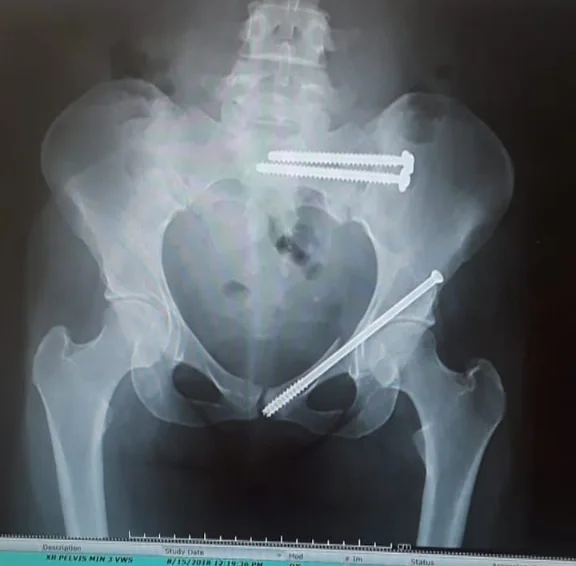

Таз после операции